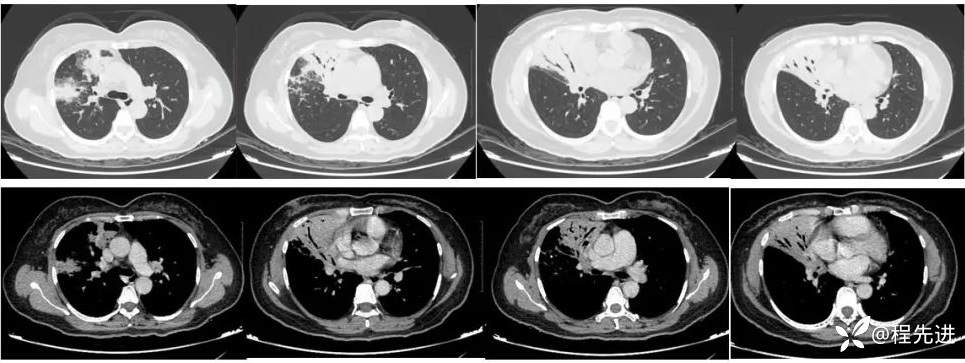

直接CT增强: